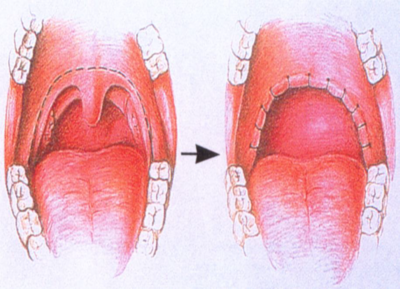

人は通常上気道を広げる筋肉が緊張していて、気道を広げて、呼吸している。眠りが深くなるとこの緊張が解けて、気道が狭くなるとともに、舌の根元がのど側に下がって食道と気道とを切り替えている軟口蓋を塞ぎ、気道が狭くなり、いびきが生じ、これがはなはだしい場合、気道が閉じて無呼吸となる。

- 下あごが小さく口の中に舌の収納空間が狭い人

- 舌や舌の付け根が大きく、結果的に口の中に舌の収納空間が狭い人